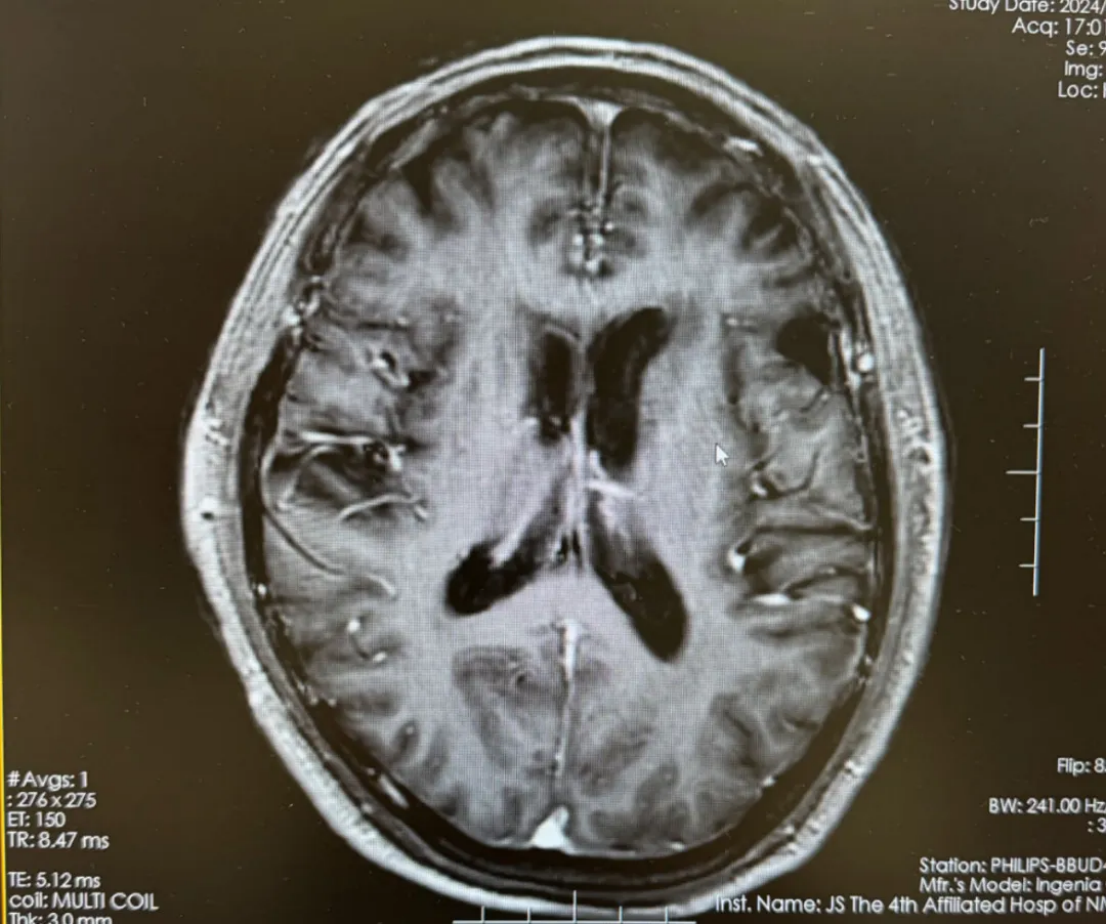

开始给予恩沃利单抗200mg d1、8+伊立替康100mg d1、8+替尼泊苷50mg d1,2,8,9方案化疗,过程顺利。2023-10-12化疗2周期,复查头颅磁共振平扫提示,左侧额叶占位性病变,大小约1.7cm*1.7cm,较前片(2023-08-15)病灶及周围水肿明显缩小;脑内多发缺血腔梗灶;老年性脑改变(图2)。2023-11-08替尼泊苷末次治疗,患者情况稳定,主观评价良好,实现PR。

图2 化疗2周期复查头颅磁共振平扫